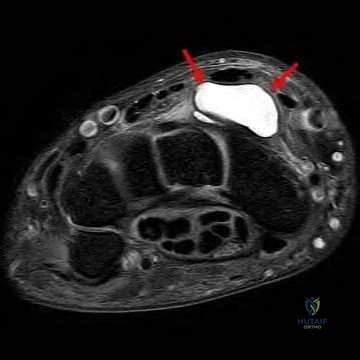

Question 12:

A runner presents with chronic, recalcitrant heel pain. A nerve block of the first branch of the lateral plantar nerve (Baxter's nerve) completely resolves his pain temporarily. If left untreated and compression worsens, which of the following muscles would primarily demonstrate denervation changes on an MRI?

Options:

- Abductor hallucis

- Flexor digitorum brevis

- Quadratus plantae

- Abductor digiti minimi

- Adductor hallucis

Correct Answer: Abductor digiti minimi

Explanation:

Baxter's nerve is the first branch of the lateral plantar nerve. It courses between the deep fascia of the abductor hallucis and the medial aspect of the quadratus plantae, then beneath the calcaneus to supply the abductor digiti minimi muscle. Entrapment causes heel pain mimicking plantar fasciitis and can lead to atrophy of the abductor digiti minimi.